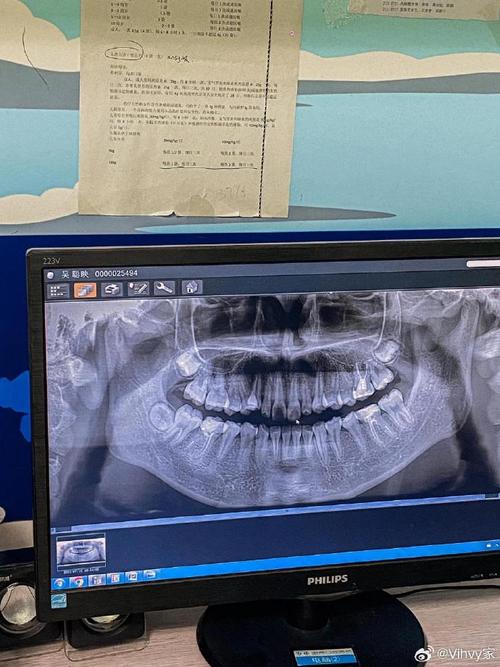

| 全景片(曲面断层片) | 全口牙齿、牙槽骨、颌骨、颞下颌关节、上颌窦、下颌神经管等 | 观察牙齿数量(是否有埋伏牙、多生牙、缺失牙)、牙根形态、牙槽骨密度、骨皮质厚度等,初步判断颌骨内是否有病变。 |

| 根尖片 | 单颗或少数几颗牙齿的牙根、根尖周组织及牙槽骨的影像 | 配合全景片,进一步观察个别牙牙根形态(如弯曲、短根)、根尖是否有炎症、牙槽骨吸收情况,排除矫正禁忌证。 |